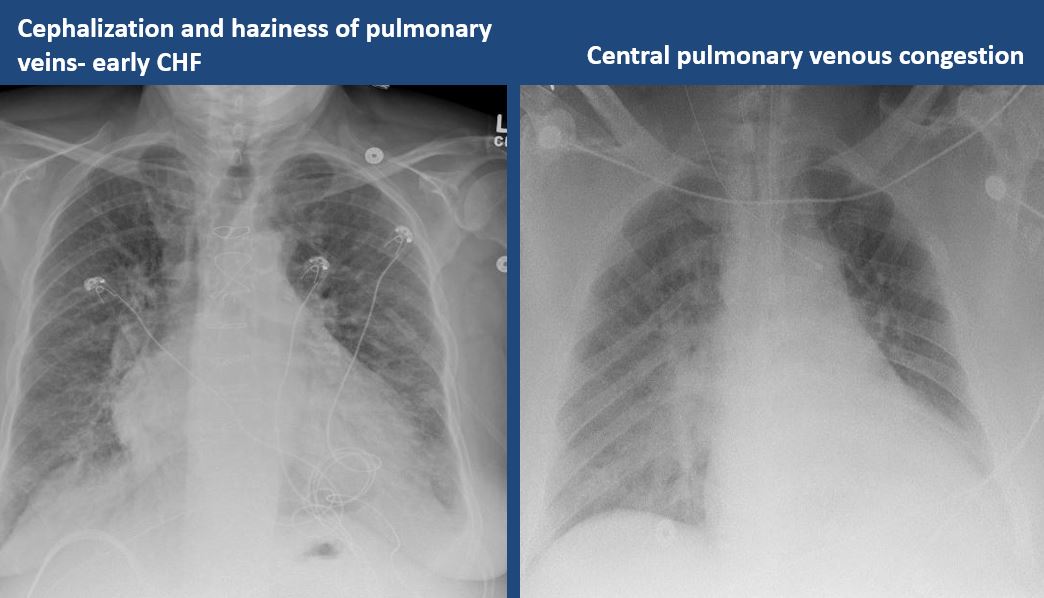

There is cephalization or haziness of the pulmonary vessels or congestion of the central pulmonary vasculature. [Yes/No]